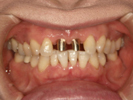

50代女性

歯がこのままではダメだと思い、一念発起された50代女性の方です。

もちろん治療期間が長期にかかることも、治療費が高額になることも、外科的な手術が何度か必要であることなど、

インプラント治療と咬み合わせ治療のほぼ全てを大名歯科ホームページで予め知っていただいた上で決心され来院されたそうです。

インプラント治療は顎骨が乏しかったため、増骨手術も併用しなければならない難症例でした。

治療期間中は残存歯数が少ない上に、丈夫でないため生活に不自由な点がでました。

さらに咬み合わせが安定しにくい症例のため、プラスチック仮歯がよく壊れたり、外れたりして、修理に来院していただくなど大変な苦労とご迷惑をおかけしました。

審美性(見た目)は十分回復できたと思っており、患者さんも大変満足されています。

食事は当然のことかもしれませんが、よく咬めるようになったそうです。

咬み合わせ治療は非常に難しいため、これで十分かどうか分かりませんが現在もこのまま定期的なメインテナンス中です。